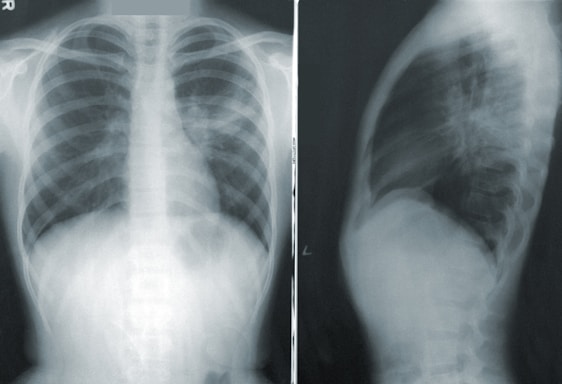

Right now, spiral CT scans are the go-to for high-risk individuals—but Paula’s Test offers something big: no radiation, fewer false alarms, wider access, and a shot at spotting lung cancer before it even shows up on a scan.